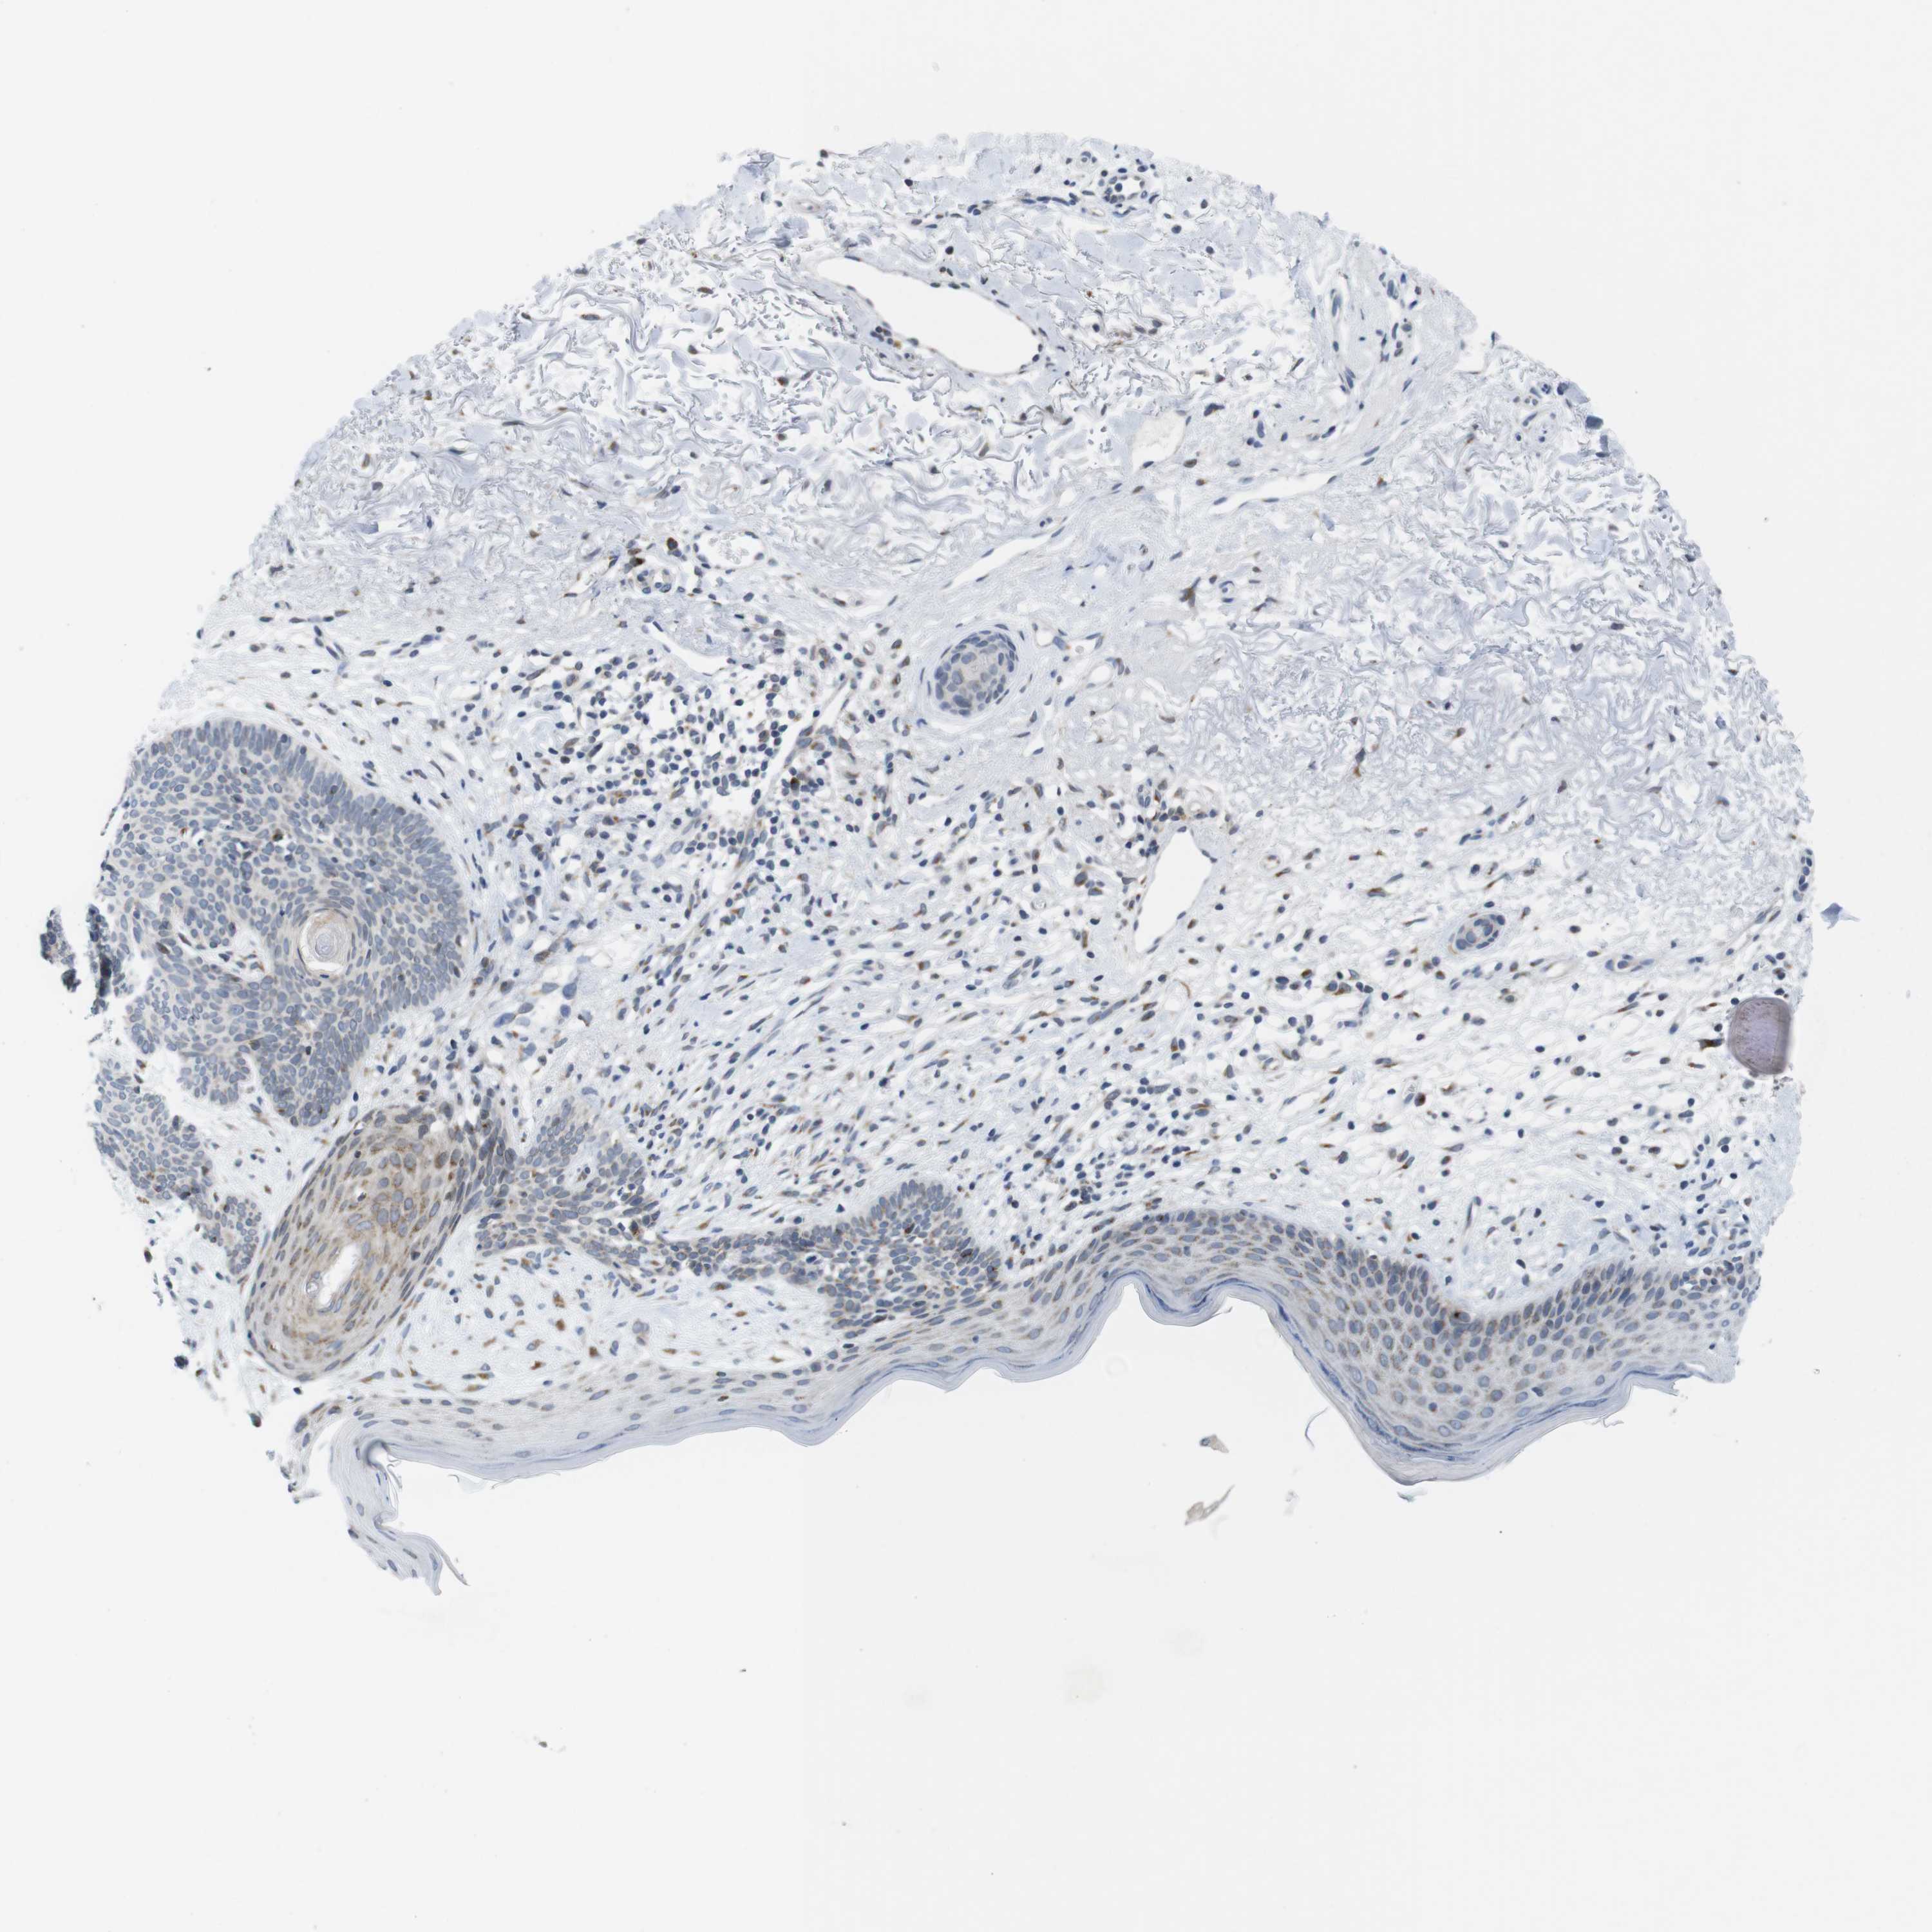

SKIN CANCER - Protein expressioni

A mouse-over function shows sample information and annotation data. Click on an image to view it in a full screen mode. Samples can be filtered based on level of antibody staining by selecting one or several of the following categories: high, medium, low and not detected. The assay and annotation is described here.

Each image is clickable and will lead to virtual microscopy that enables deeper exploration of all samples and also displays staining intensity scores, fraction scores and subcellular localization as well as patient and tissue information for each sample.

Antibody HPA015242

Basal cell carcinoma